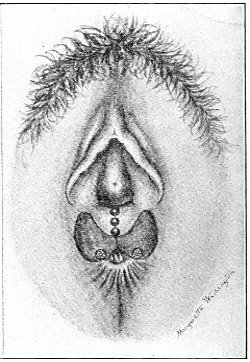

Suppuration of the vulvo-vaginal gland is accompanied by marked swelling and peripheral edema. The swelling may extend to the anus, and is of characteristic shape (Fig. 17). The pain is always severe. Fluctuation is first apparent on the inner surface of the labium majus. If the condition is not treated, one or more fistulous openings appear below the orifice of the duct, and the pus is discharged. The condition then becomes chronic. The fistulous openings persist. Acute inflammation disappears from the gland, leaving it in a condition of hypertrophic induration. A thin, milky or greenish, purulent fluid may be pressed out of the duct or the fistulous openings. Infection from this discharge may be communicated to man, or may ascend the genital 40 tract, producing inflammation of the endometrium or of the Fallopian tubes.

Fig. 17.—Abscess of right vulvo-vaginal gland.